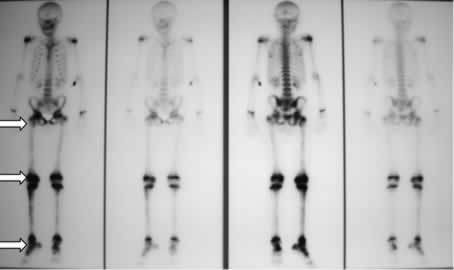

Quello che colpiva nella valutazione della diagnostica per immagini era l'aspetto, in corso di scinti- grafia, di ipercaptazione di tutto il femore, non solo delle articolazioni, dato che peraltro, vista la evidenza di artrite concomitante, non era stato particolarmente valorizzato pensando ad una generica “ipersensibilità” della scintigrafia. (figura 1)

Figura 1: riscontro di zone multiple di captazione (ginocchio, articolazione tibio-tarsica, femore destro e coxo-femorale destra).